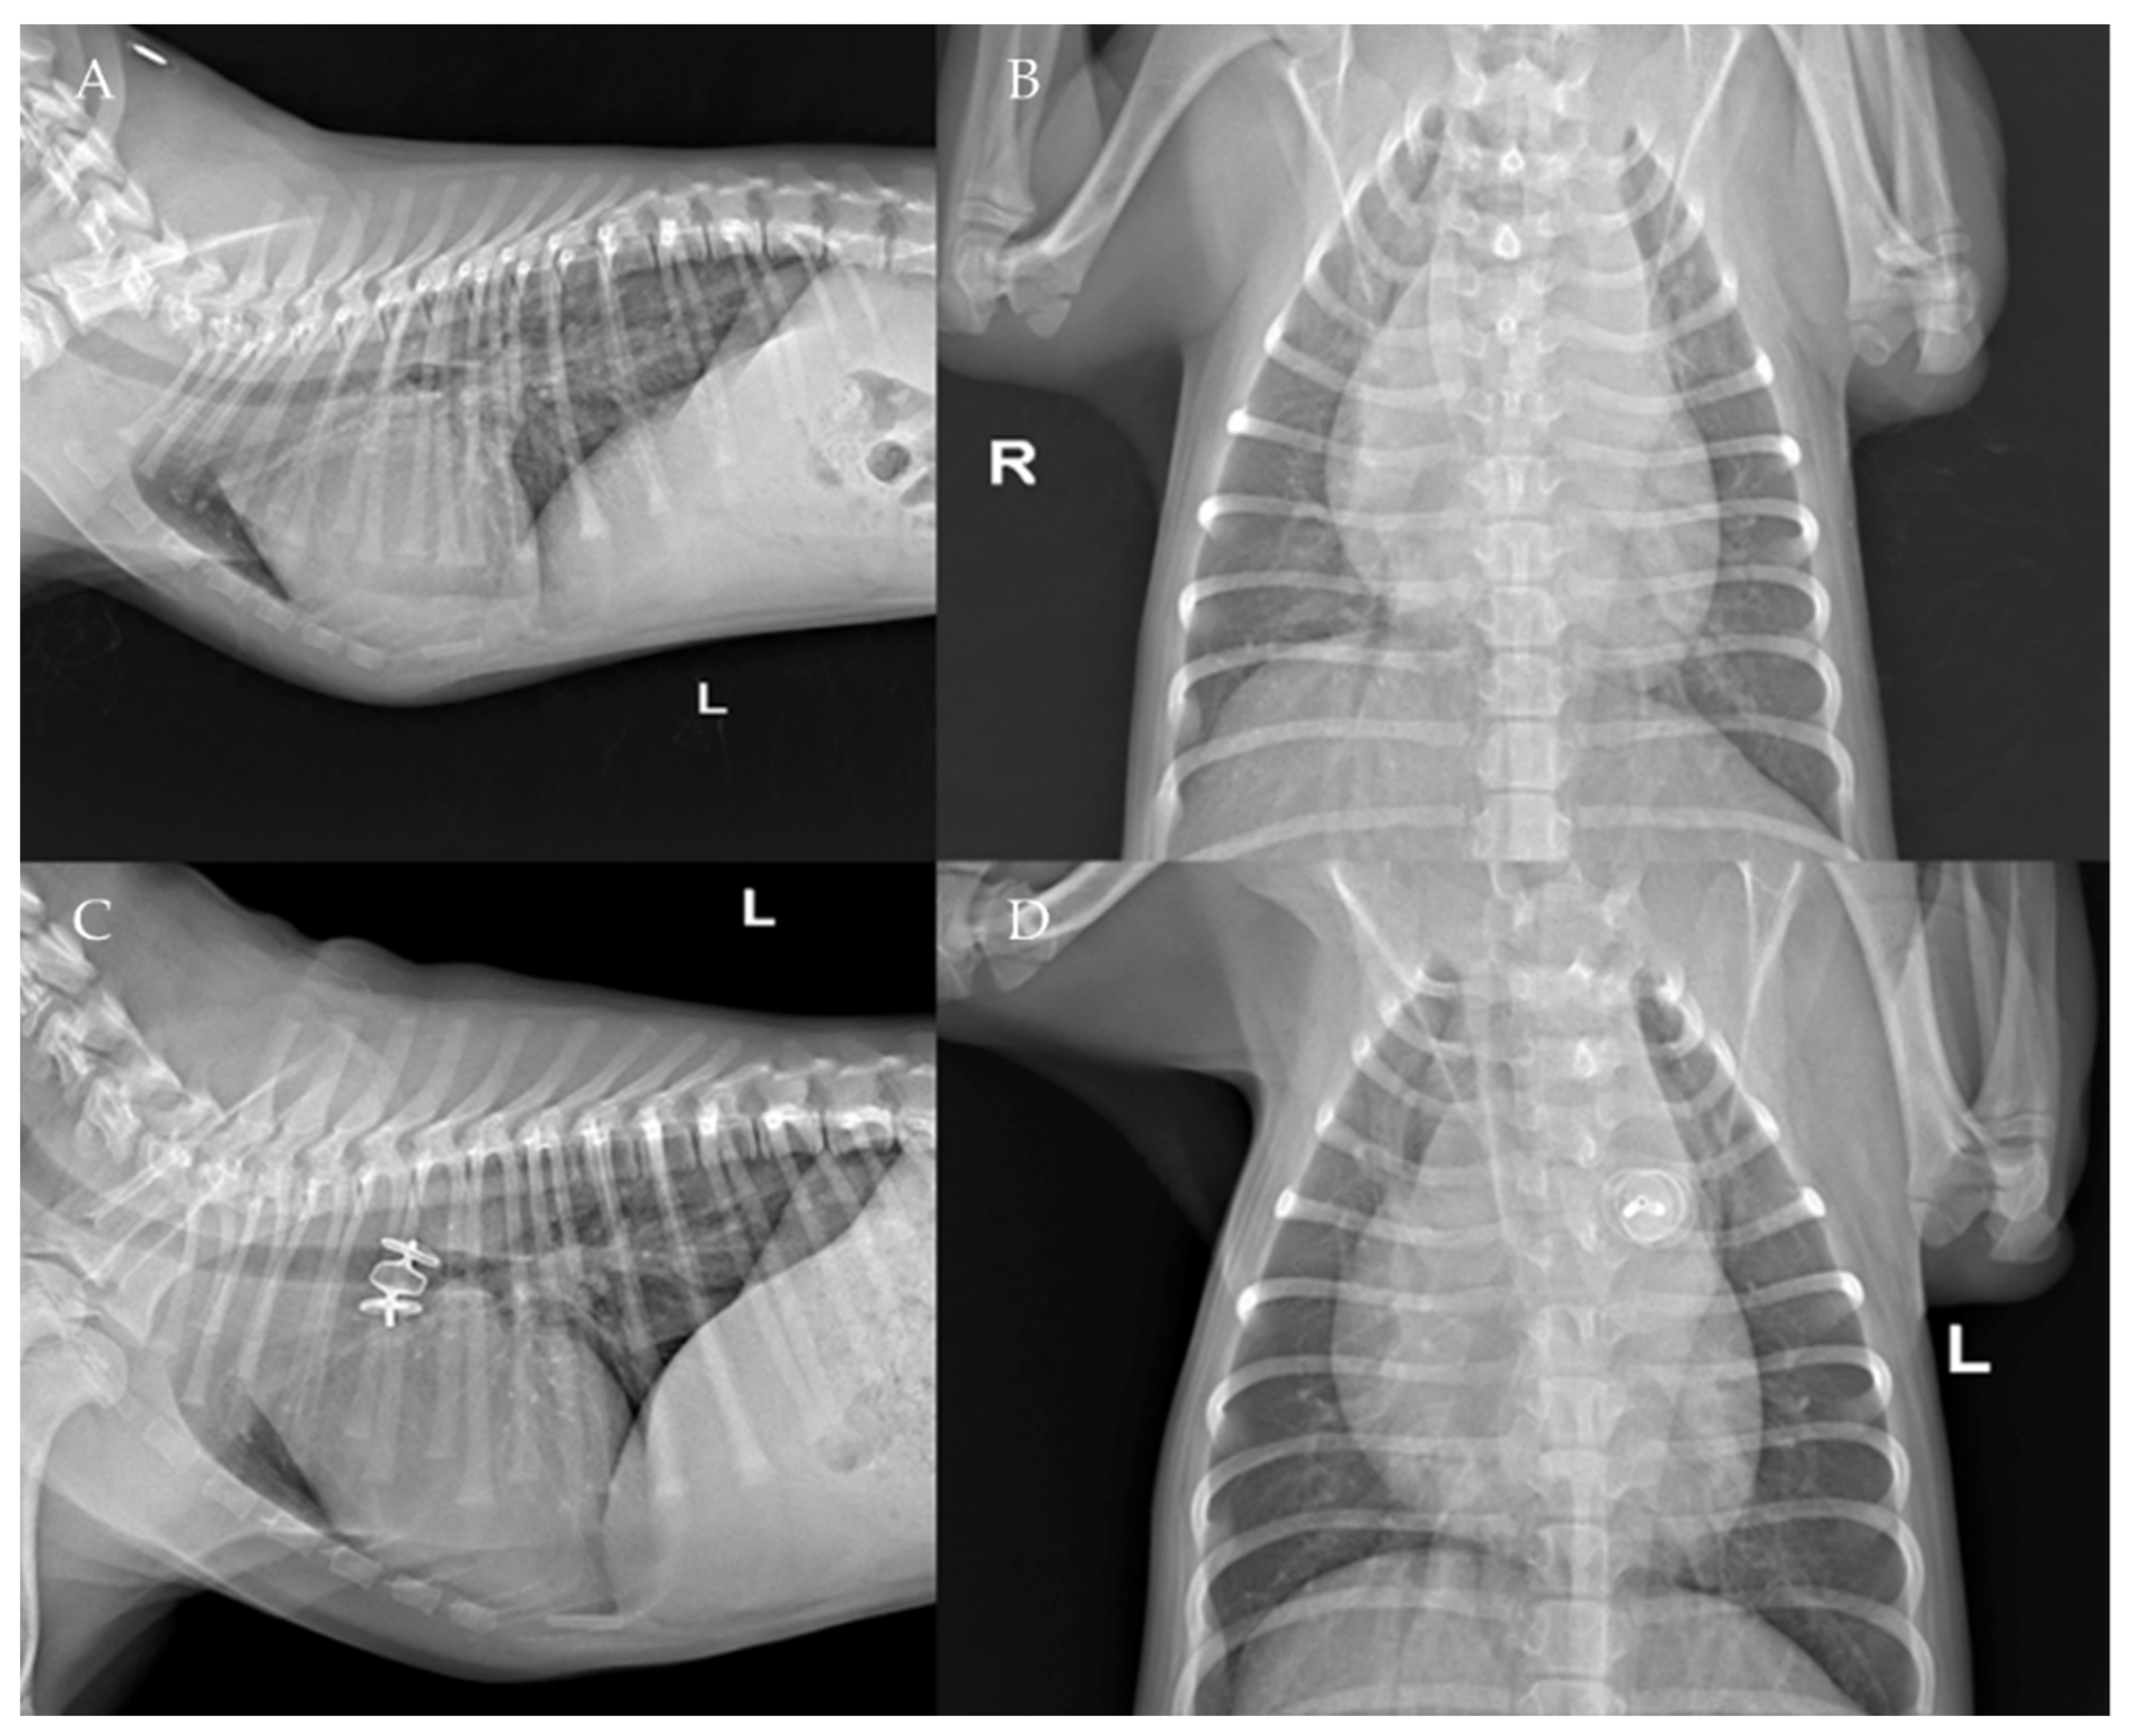

The AVP II device was then detached by counterclockwise rotation of the delivery wire. All catheters were then removed, and the right jugular vein was sutured with 4-0 monofilament polydioxanone absorbable suture (PDSII Ethicon) or ligated [30]. Post-operative thoracic radiography confirmed the correct placement of the device in all patients (Figure 6).

The thoracic radiographs performed before and just after the procedure showed a reduction in the cardiac silhouette as well as significant reduction of the over-circulation vascular pattern for all dogs (Figure 8, Figure 9, Figure 10, Figure 11 and Figure 12).

Figure 8. Pre-procedure (A,B) and post-procedure (C,D) left lateral and dorso-ventral thoracic radiographs of Case 1. L: left; R: right.